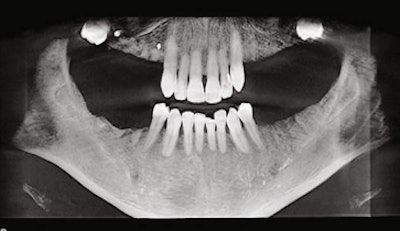

Panoramic radiograph (circa 2016) taken before extractions.

Panoramic radiograph (circa 2016) following extraction of all posterior teeth except the mandibular first bicuspids. Impacted third molars were not removed due to the distinct possibility of ankylosis and the potential for fracturing the posterior wall and floor of the maxillary antrum.

Panoramic radiograph (March 2017) after placement of dental implants and treatment planned for a shortened dental arch.